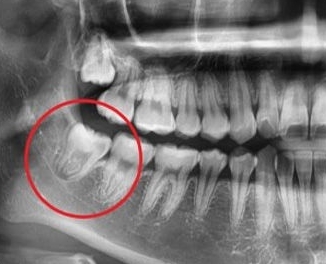

사랑니가 나오는 방향, 위치, 각도가 올바르지 못해 통증과 붓기를 유발하여 불편함 초래

일상생활의 불편함사랑니가 나오는 방향, 위치, 각도가 올바르지 못해 통증과 붓기를 유발하여 불편함 초래

똑바로 자라난 사랑니는 문제가 없다면 굳이 발치하지 않아도 되지만

붓고 피나며 통증으로 구강관리에 어려움을 느낀다면 제거하는 것이 좋습니다.

사랑니 발치는 간단히 제거되는 경우도 있지만 대학병원을 권유 받을

난이도가 높은 경우도 있습니다.

사랑니가 나오는 방향, 위치, 각도가 올바르지

못해 통증과 붓기를 유발하여 불편함 초래